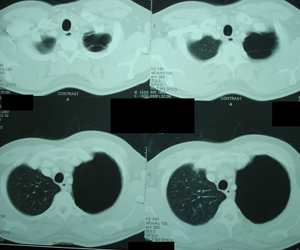

Εικόνα 2α

Αξονική τομογραφία του θώρακος. Τομή στο επίπεδο της κορυφής των

Πνευμόνων. Αερώδεις κύστες που καταλαμβάνουν εξ΄ολοκλήρου το

αριστερό άνω πνευμονικό πεδίο.

Εικόνα 2β

Αξονική τομογραφία θώρακος. Τομή στο επίπεδο της τρόπιδας και στο

ύψος των κυρίων βρόγχων. Πάλι το αριστερό ημιθωράκιο συνεχίζει να

καταλαμβάνεται από αερώδεις κύστες.